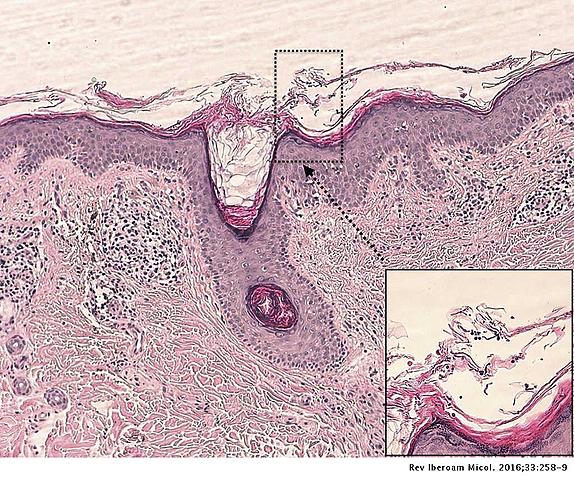

• PITIRIASIS VERSICOLOR

PITIRIASIS VERSICOLOR

Eichstedt describió por primera vez el componente micótico de las lesiones de la pitiriasis versicolor.